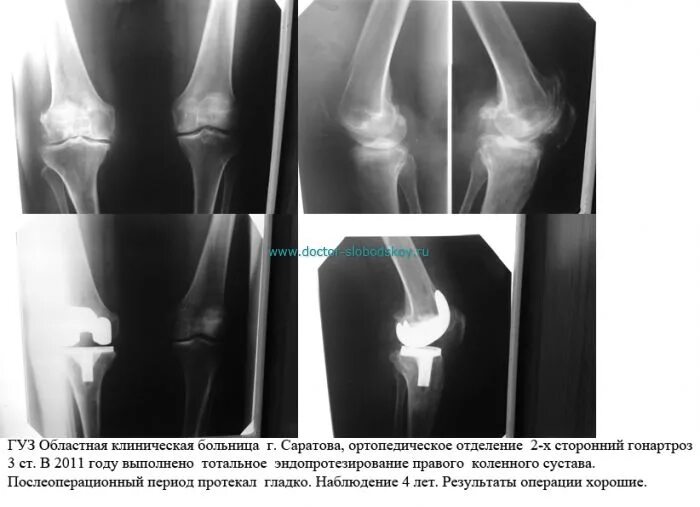

Гонартроз мрт